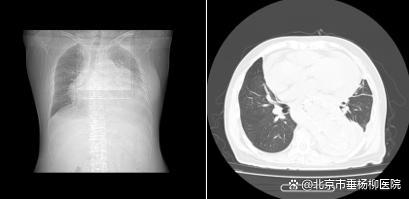

图表1一位长期透析不充分的女性患者